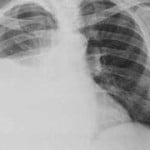

28 GEN – Un caso di sospetta Tbc in un bambino con meno di 5 anni, che frequenta un asilo nido di Ferrara citta’. In base alla segnalazione ha preso avvio, come da protocollo nazionale, l’attivita’ di screening su tutti i contatti, familiari e non familiari.

Lo rende noto un comunicato dell’Ausl di Ferrara. Il caso e’ stato segnalato alla Regione ed e’ partito il protocollo di sorveglianza della malattia, in base alle linee guida in materia. Il protocollo prevede il controllo dei ‘contatti’ del caso, anche se sospetto, con test cutanei e/o su sangue. (ANSA)